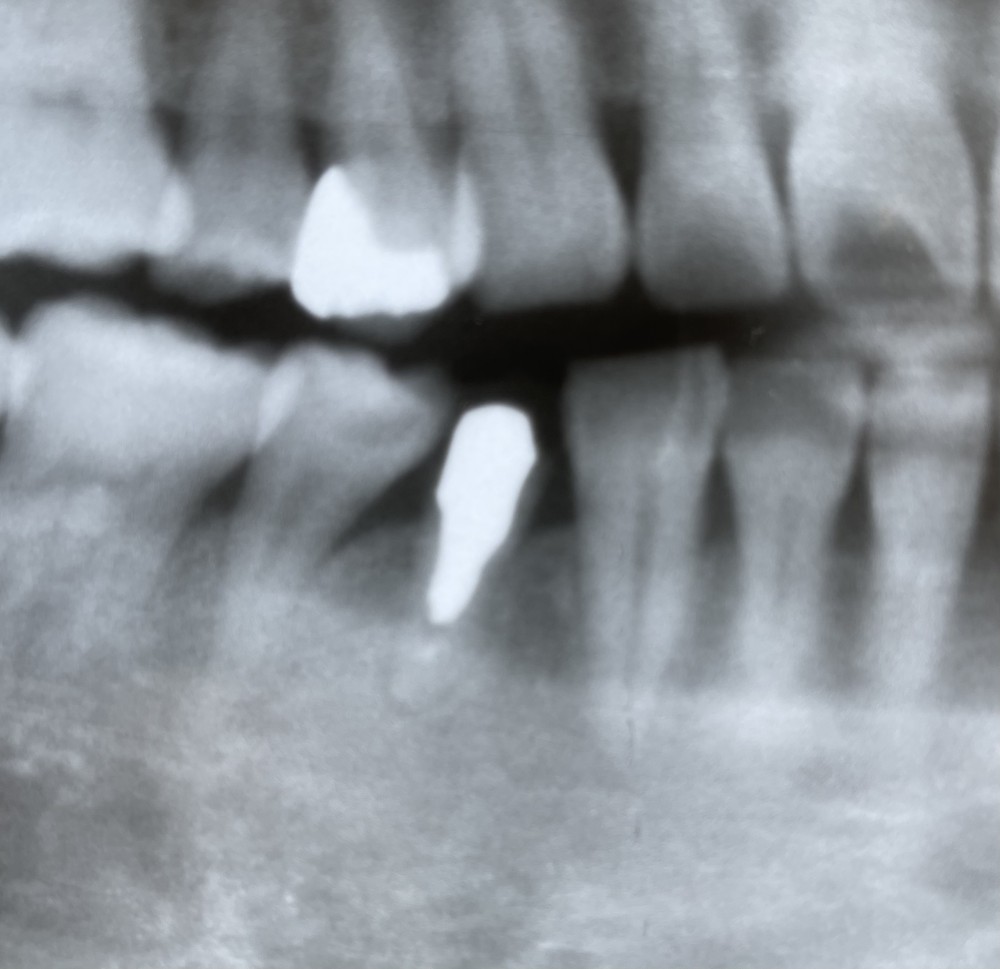

下の写真は、初診時から11年経過後のエックス線写真です。

↓↓↓↓↓↓↓↓↓↓↓

今のところ、右下4も、右上4も経過良好です。

右下5カリエスは、今後治療予定です。

右下4は、HJKですが、案外長持ちしています。